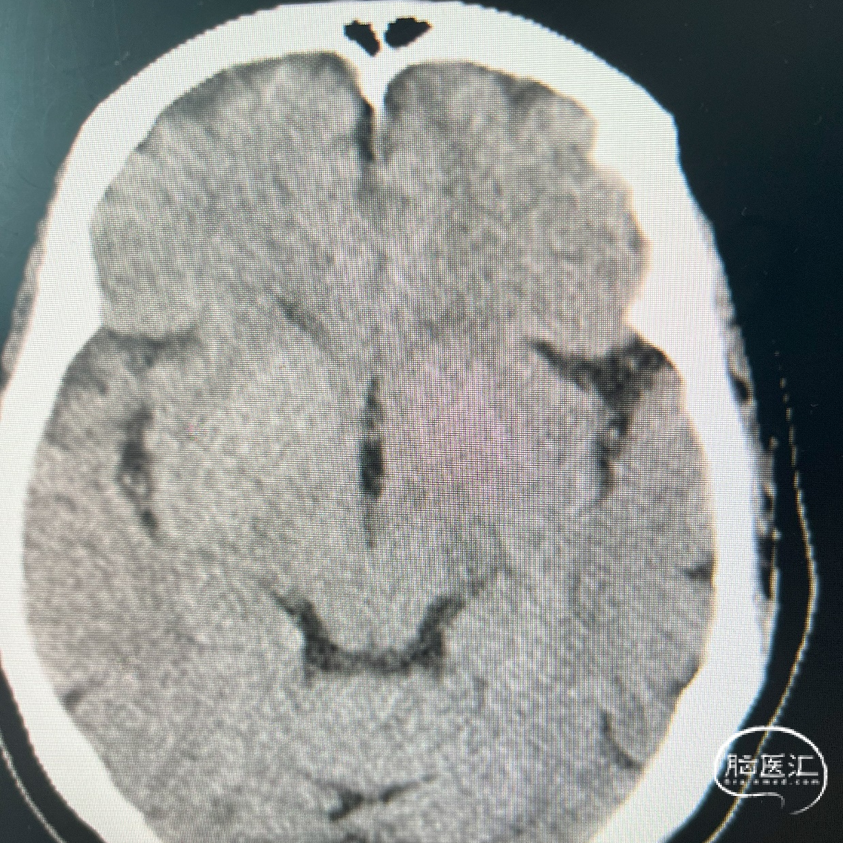

术前影像资料

术前辅助检查:

术前FLAIR

术前DWI

术前MRA

影像学表现:

1、主动脉弓及其他弓上血管,III型弓,弓上血管迂曲,血管通畅。

2、颈内动脉系统:

右侧颈总动脉及颈内动脉血管通畅,远端右侧大脑中动脉血流通畅,可见同侧及对侧大脑前动脉显影。

左侧颈总动脉及颈内动脉血流通畅,后交通开放,可见同侧大脑后动脉显影,大脑前动脉血流通畅。

3、椎基底动脉系统:

右侧椎动脉优势型。

左侧椎动脉血管纤细,远端可见基底动脉浅淡显影。

右侧椎动脉优势型,远端汇入基底动脉。

基底动脉中段重度狭窄,狭窄率约80%,双侧大脑后动脉可见显影。